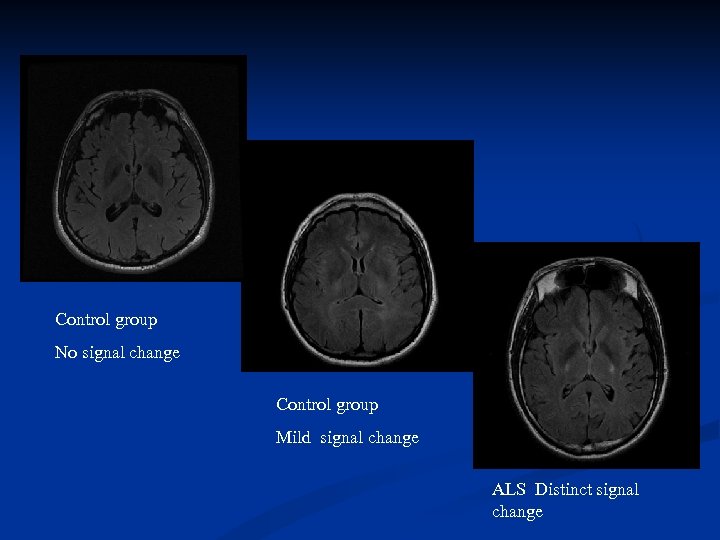

Signal changes were visually evaluated by three experienced neuroradiologists in consensus, blinded to the clinical results. MRI findings evaluated: T 2 FLAIR signal changes in the PLIC Signal changes are classified (*) as • no signal change • “mild” hyperintense if the signal was isointense or of similar intensity to the caput of the caudate nucleus • “distinct” hyperintense if the signal was isointense or of similar intensity to the insular cortex, Fractional anisotropy (FA) measurements are performed by placing a region of interest (ROI) in PLIC bilaterally. Both findings are being compared. (* Hecht MJ, Fellner F, Fellner C, Hilz MJ, Heuss D, Neundörfer B. MRI-FLAIR images of the head show corticospinal tract alterations in ALS patients more frequently than T 2 -, T 1 - and proton-density-weighted images. J Neurol Sci. 2001 May 1; 186(1 -2): 37 -44. )

Signal changes were visually evaluated by three experienced neuroradiologists in consensus, blinded to the clinical results. MRI findings evaluated: T 2 FLAIR signal changes in the PLIC Signal changes are classified (*) as • no signal change • “mild” hyperintense if the signal was isointense or of similar intensity to the caput of the caudate nucleus • “distinct” hyperintense if the signal was isointense or of similar intensity to the insular cortex, Fractional anisotropy (FA) measurements are performed by placing a region of interest (ROI) in PLIC bilaterally. Both findings are being compared. (* Hecht MJ, Fellner F, Fellner C, Hilz MJ, Heuss D, Neundörfer B. MRI-FLAIR images of the head show corticospinal tract alterations in ALS patients more frequently than T 2 -, T 1 - and proton-density-weighted images. J Neurol Sci. 2001 May 1; 186(1 -2): 37 -44. )

Control group No signal change Control group Mild signal change ALS Distinct signal change

Control group No signal change Control group Mild signal change ALS Distinct signal change